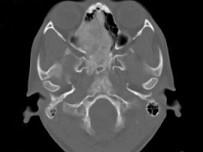

女,17岁,鼻阻塞、头痛两年.如图所示符合筛骨病变最可能的诊断是 ( )

• A.成骨肉瘤

• B.骨瘤

• C.骨化性纤维瘤

• D.软骨瘤

• E.纤维异常增殖症

答案: C